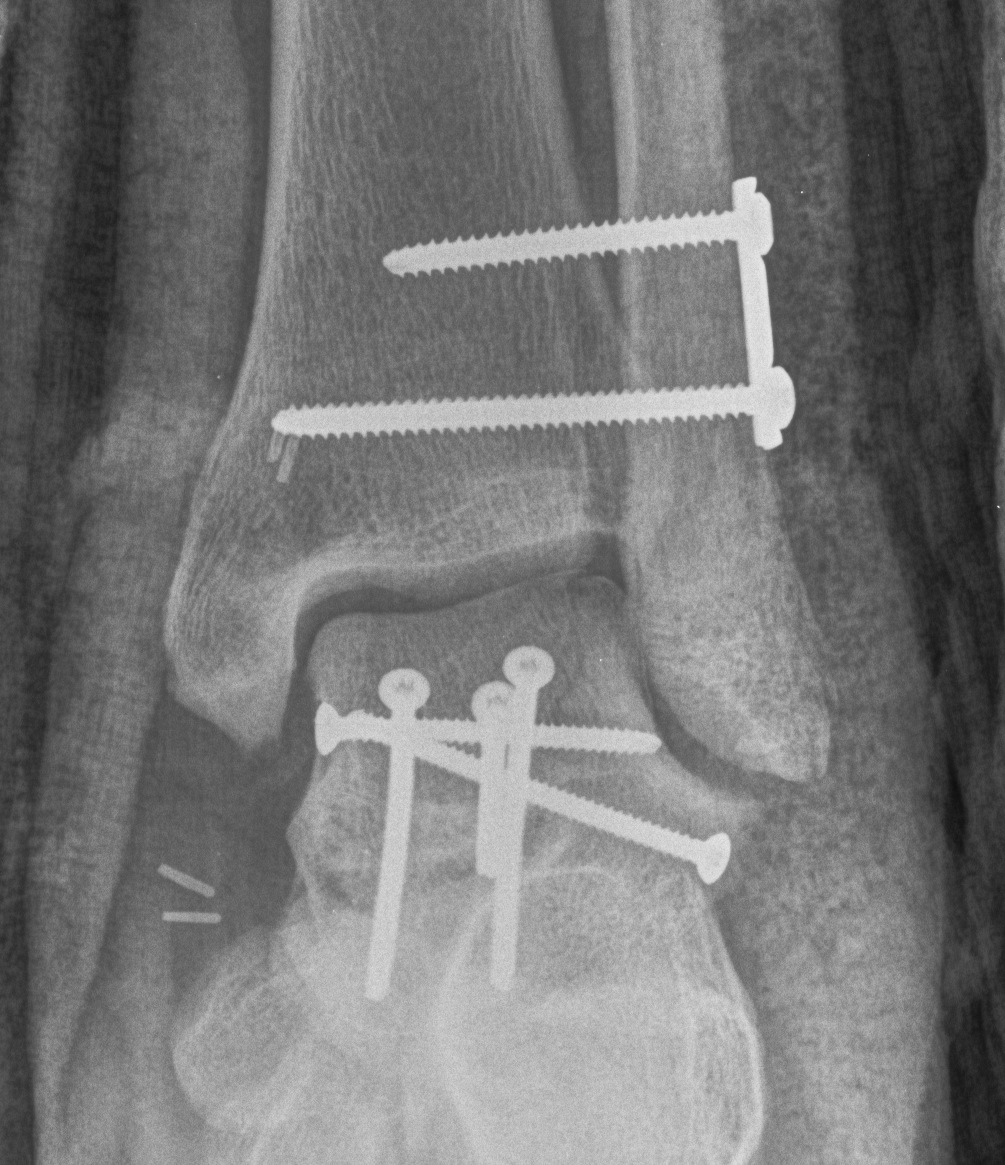

Cannulated screws

Xrays

| AP | Lateral | Canale View |

|---|---|---|

| Entry point of the screws |

Evaluate neck reduction

|

Evaluates the neck reduction |

Lateral off articular surface Medial through articular cartilage |

Depth of screws |

Beam angled 75o to foot Foot 15o pronated |

1. Retrograde (anterior to posterior) into posterior talus body

A. Lateral screw

- insert proximal to articular surface of head on lateral side

- bone is very curved here

- can lag screw as usually no comminution

B. Medial side

- insert through articular surface

- countersunk screws through articular surface

- avoid lag screw techniques medially as may compress comminution into varus

AP, Canale and Lateral xray

Retrograde screws